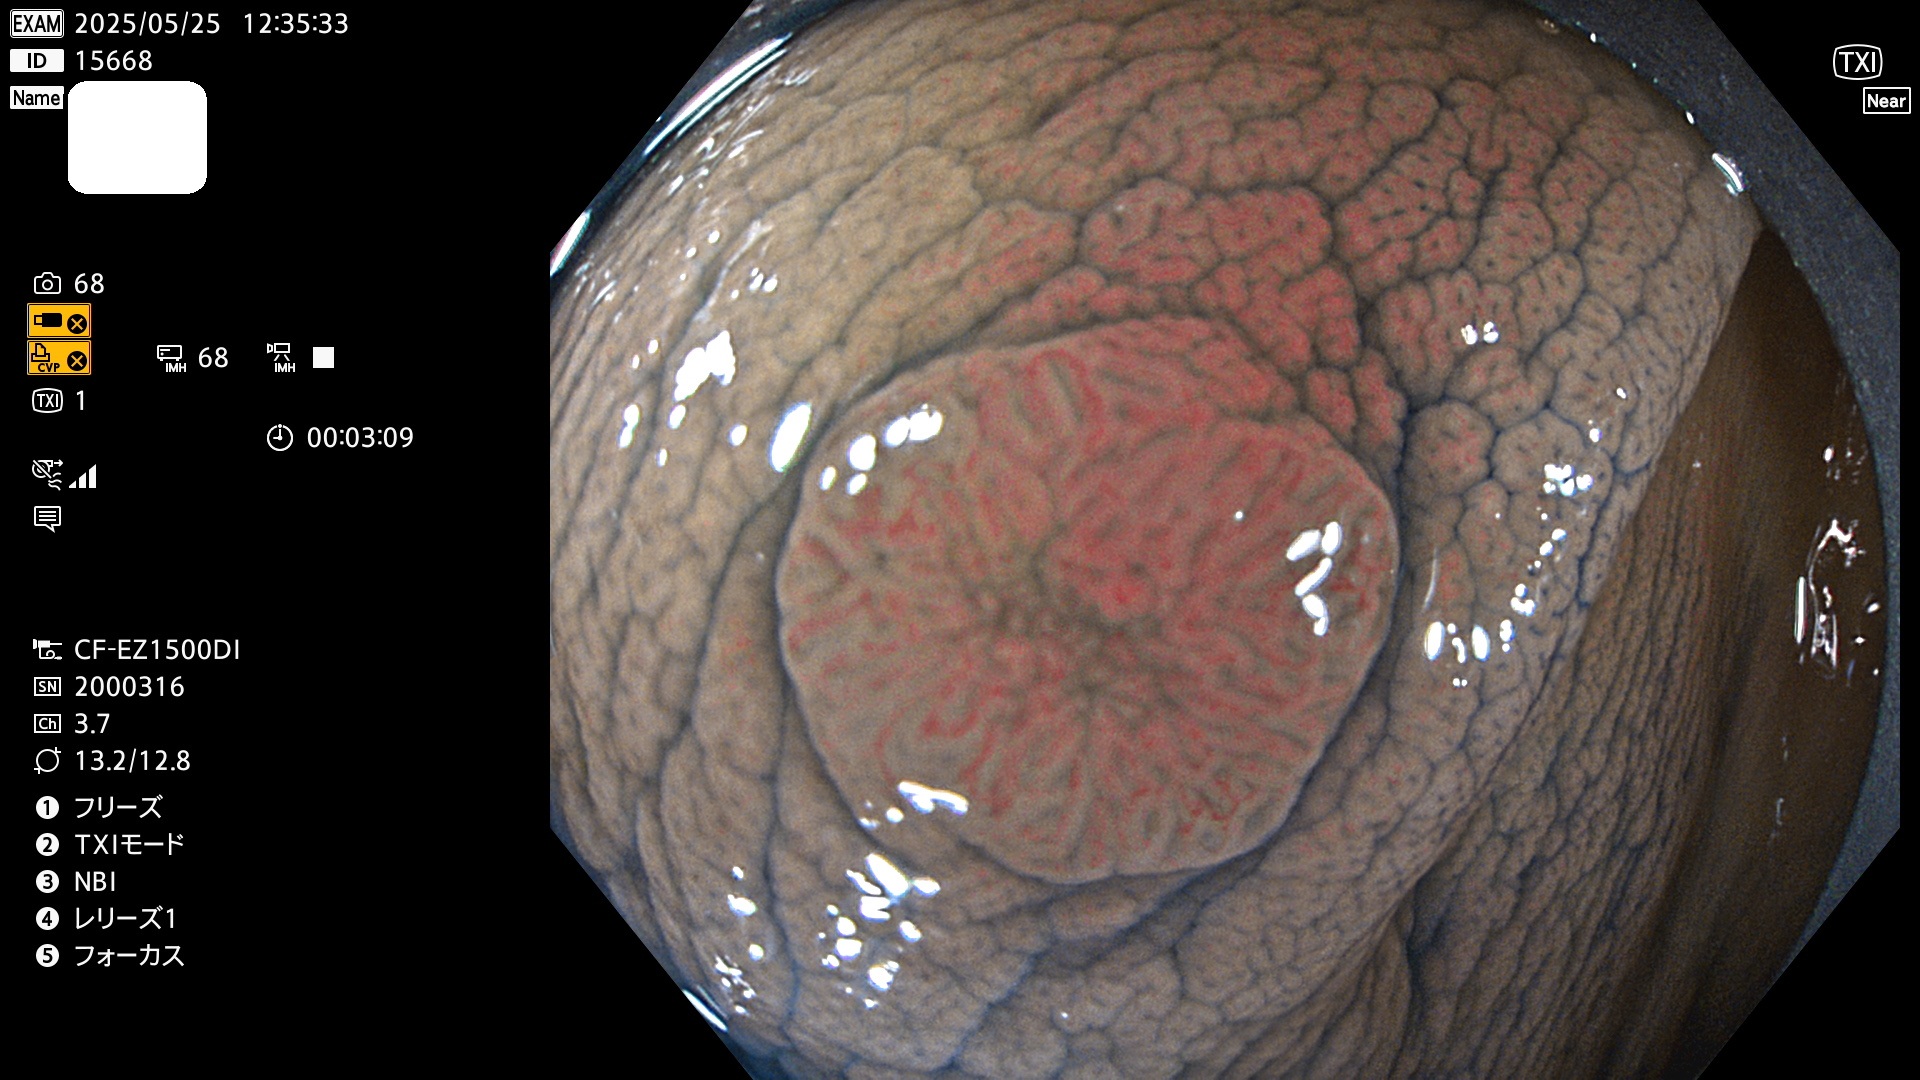

今週のUb、Uc型腺腫

完全に平坦な物をUb、陥凹している物をUcと呼びます。Ubは認識が困難で、Ucはびらん(炎症)と紛らわしいために見落とされやすく、「内視鏡後・大腸癌」の原因になります。

抽出の対象期間 2025年5月22日〜5月25日の4日間(48件の検査)10個 (10/48=21%)